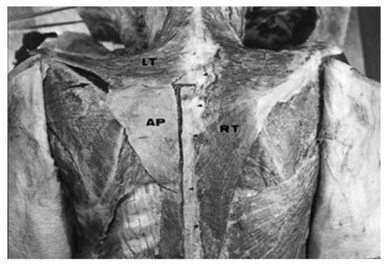

Garbelotti et al.17 have reported the case of a partial and unilateral absence of the trapezius muscle discovered during dissection of an adult black male cadaver. The detailed examination showed that the ascending part of the trapezius and the descending fibers of the middle part were replaced by a broad 2mm thick fascia. Histological analysis showed the presence of a few muscle fibres in the aponeurosis.

From a functional view point, it was possible that this individual would have had difficulty in moving his shoulder, especially during flexion, abduction and circumduction of the arm Figure 4.

Gross-Kieselstein et al.19 also reported a study in which 2 parents had a complete absence of trapezius muscle. The first case is that of a 17year-old teenager presenting with a complete lack of muscular structure on the trapezius in the back region, and on the area of the pectoralis major in front (Figure 5). The second case concerns the older brother of the first case. Aged of 28, he had an absence of trapezius muscles and pectoralis major only on the right side.

Figure 5 Dorsal view showing the normal right trapezius (RT), the descending fibres and part of the transverse fibres of the left trapezius (LT), and an aponeurosis replacing the ascending fibres of the left trapezius (AP). The aponeurosisattachs to C7 and T1-T6 (short arrows), rhomboid major (RM) and spine of the scapula (long arrow).17